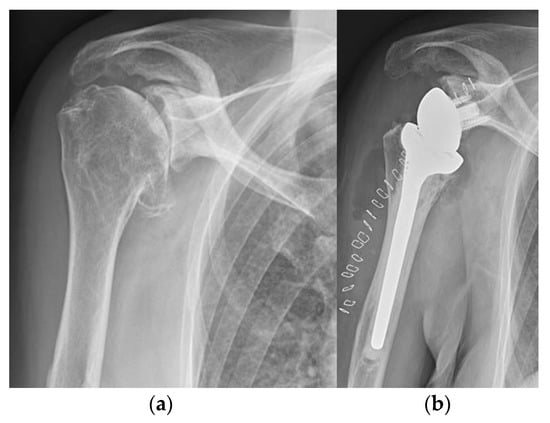

5.2. Shoulder

5.3. Elbow